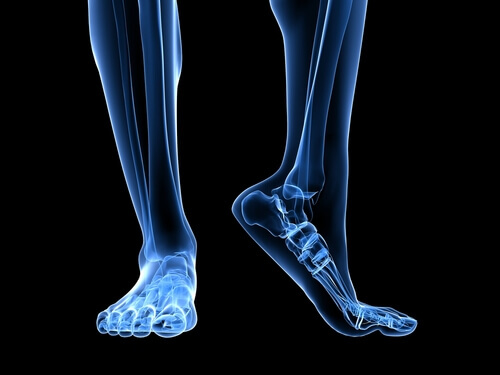

Ανατομία του ποδιού

Υπάρχουν αρκετές ανατομικές δομές που παίζουν ρόλο στην καταπόνηση της πελματιαίας περιτονίας.

Ο αχίλλειος τένοντας είναι ένας σύνδεσμος που συνδέει τους γαστροκνημίους μύες, που είναι γνωστοί ως μύες της γάμπας, και τους υποκνημιδίους μύες με το οστό της φτέρνας. Η σύσπαση του αχίλλειου τένοντα προκαλεί αύξηση της πίεσης στο οστό της φτέρνας, με αποτέλεσμα να αυξάνεται η πίεση στην πελματιαία περιτονία.

Ένας άλλος παράγοντας που πρέπει να έχουμε υπόψη αναφορικά με την ανατομία είναι ο πρηνισμός, ή με άλλα λόγια το πώς το πέλμα έρχεται σε επαφή με το έδαφος. Τα πέλματα με πλατυποδία ή με τάση υπερπρηνισμού τεντώνουν ακόμα περισσότερο την πελματιαία περιτονία, αυξάνοντας έτσι τον κίνδυνο ρήξεων λόγω της επιπλέον πίεσης που ασκείται στον ιστό.